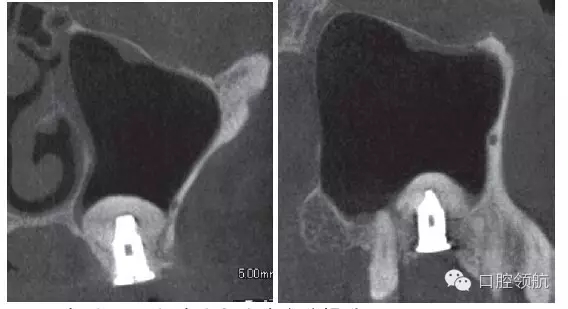

拔除(左上第六顆牙)后,抗生素(500mg)口服1周。術(shù)后4周的CBCT顯示,上頜竇黏膜增厚明顯改善(圖3)。

圖3 拔牙后4周,上頜竇黏膜增厚消失,但仍有殘留牙槽窩。

因為垂直骨量少,在植入種植體后,為防止種植體進入上頜竇內(nèi),選擇了安裝直徑大的覆蓋螺絲(圖5、圖6)。 術(shù)后CBCT證實上頜竇底提升了足夠的骨量(圖7)。

圖7 術(shù)后CBCT證實上頜竇底充分提升。

術(shù)后12周在獲得骨結(jié)合后,開始制作上部結(jié)構(gòu),術(shù)后16周戴入(圖8)。術(shù)后24周,CBCT影像顯示,種植體周圍有足夠的骨量(圖9)。

圖9 術(shù)后24周,CBCT影像顯示通過拔牙后早期植入,能夠進行安全確實的上頜竇底提升術(shù)。